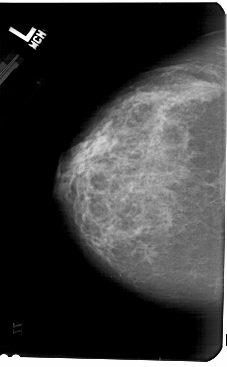

A_1569_1.LEFT_MLO

LEFT_CC LINES 5491 PIXELS_PER_LINE 3391 BITS_PER_PIXEL 12 RESOLUTION 43.5 NON_OVERLAY

LEFT_MLO LINES 5491 PIXELS_PER_LINE 3646 BITS_PER_PIXEL 12 RESOLUTION 43.5 NON_OVERLAY